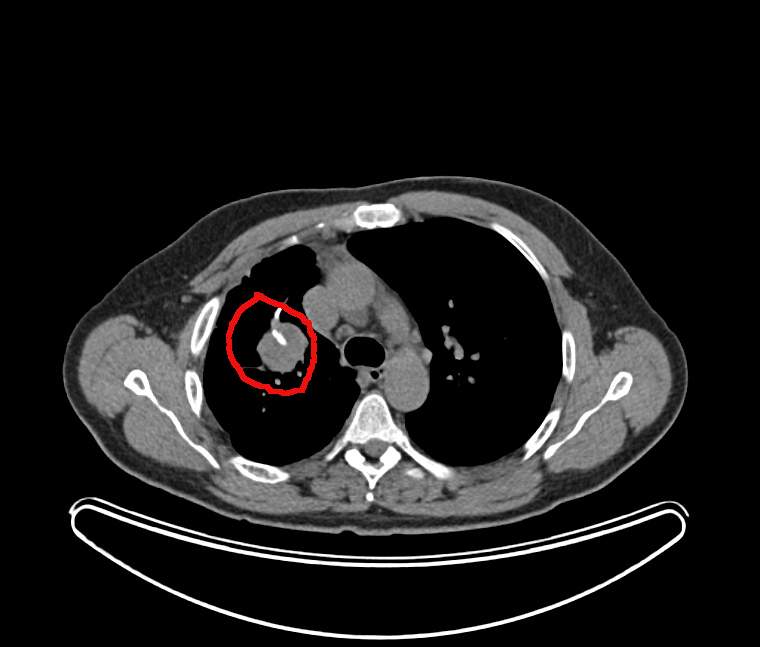

Vue de la tumeur:

il s’agit de cette grosse tache blanche dans le poumon droit (à gauche sur les images)